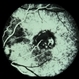

- toxocara granuloma

- Fundus photo showed central posterior granuloma on the optic nerve